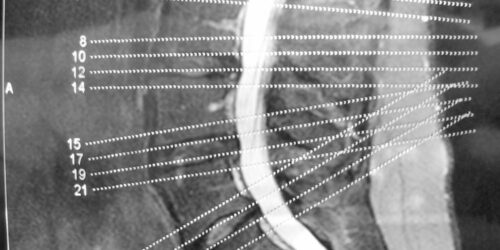

A brief overview of degenerative disc and joint disease

When you mention the term degenerative disease, it refers to the gradual deterioration of the body tissues or cells over the years due to the natural aging process. As we age, our spine starts giving in to the stress of providing flexibility and support to our back. The components of the spine start deteriorating slowly, and you will experience back pain and stiffness in the spine.